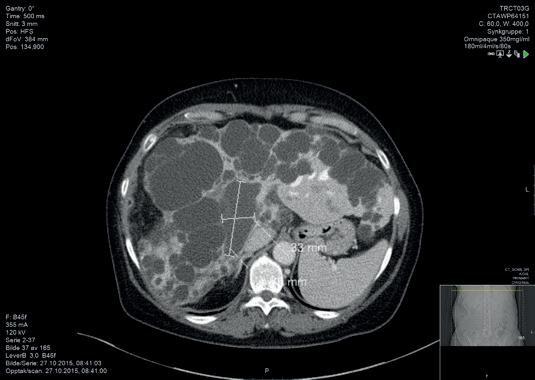

Simple levercyster kan gi symptomer i form av trykkfølelse og smerter ved matinntak. Symptomene er vanligvis relatert til cystens størrelse og beliggenhet (Figur 1), hvor cysten utøver mekanisk trykk på omgivende strukturer. Kausalitet i forhold til symptom blir viktig i vurderingen av pasientens plager; størrelse under fire cm gir sjeldent symptomer (1). Perkutan aspirasjons- og skleroterapi (PAS) er en behandlingsmetode hvor cysten dreneres og så skleroseres, typisk med etanol. Grunnet prosedyrens relativt høye effektivitet og lave komplikasjonsrisiko, bør PAS anses å være første behandling, med kirurgisk fenestrering reservert for pasienter hvor PAS ikke har ført frem (2, 3).

PAS utføres ved Oslo universitetssykehus, Rikshospitalet etter Dr. Trond Bjerke Larssens oppskrift. Bjerke Larssen var aktiv på radiologisk avdeling Haukeland universitetssykehus og disputerte på dette tema i 2006 (4). Prosedyren utføres på røntgenlaboratorium med en kombinasjon av ultralyd og røntgen (Figur 2 og 3). Kort sammenfattet utføres ultralydveiledet punksjon av cysten med innleggelse av et pigtail-dren. Ved punksjon tilstrebes det å gå gjennom leverparenchym for å unngå direkte kontakt mellom cyste og peritoneum da etanollekkasje her vil kunne føre til store smerter. Drensvæsken aspireres, cysten tømmes, og en setter så røntgenkontrast til cirka 80 % av cystevolumet for å detektere eventuell kontrastovergang til karstrukturer (levervener) eller galleganger. Dersom kontrastovergang påvises, avlyses etanolskleroseringen. Dersom ingen kommunikasjon påvises, tømmes cysten for kontrast og en setter etanol tilsvarende 10 % av cystens volum, men maksimalt 100 ml per behandling. Denne får stå i ti minutter og aspireres så ut igjen. Denne syklus gjentas én gang, før en trekker ut drenet. Flere cyster kan behandles samtidig under samme seanse hvis det er aktuelt, men fortsatt brukes da maksimalt 100 ml alkohol totalt. Det kan være aktuelt å punktere gjennom mindre cyster for å komme til en større symptomgivende cyste (Figur 4).